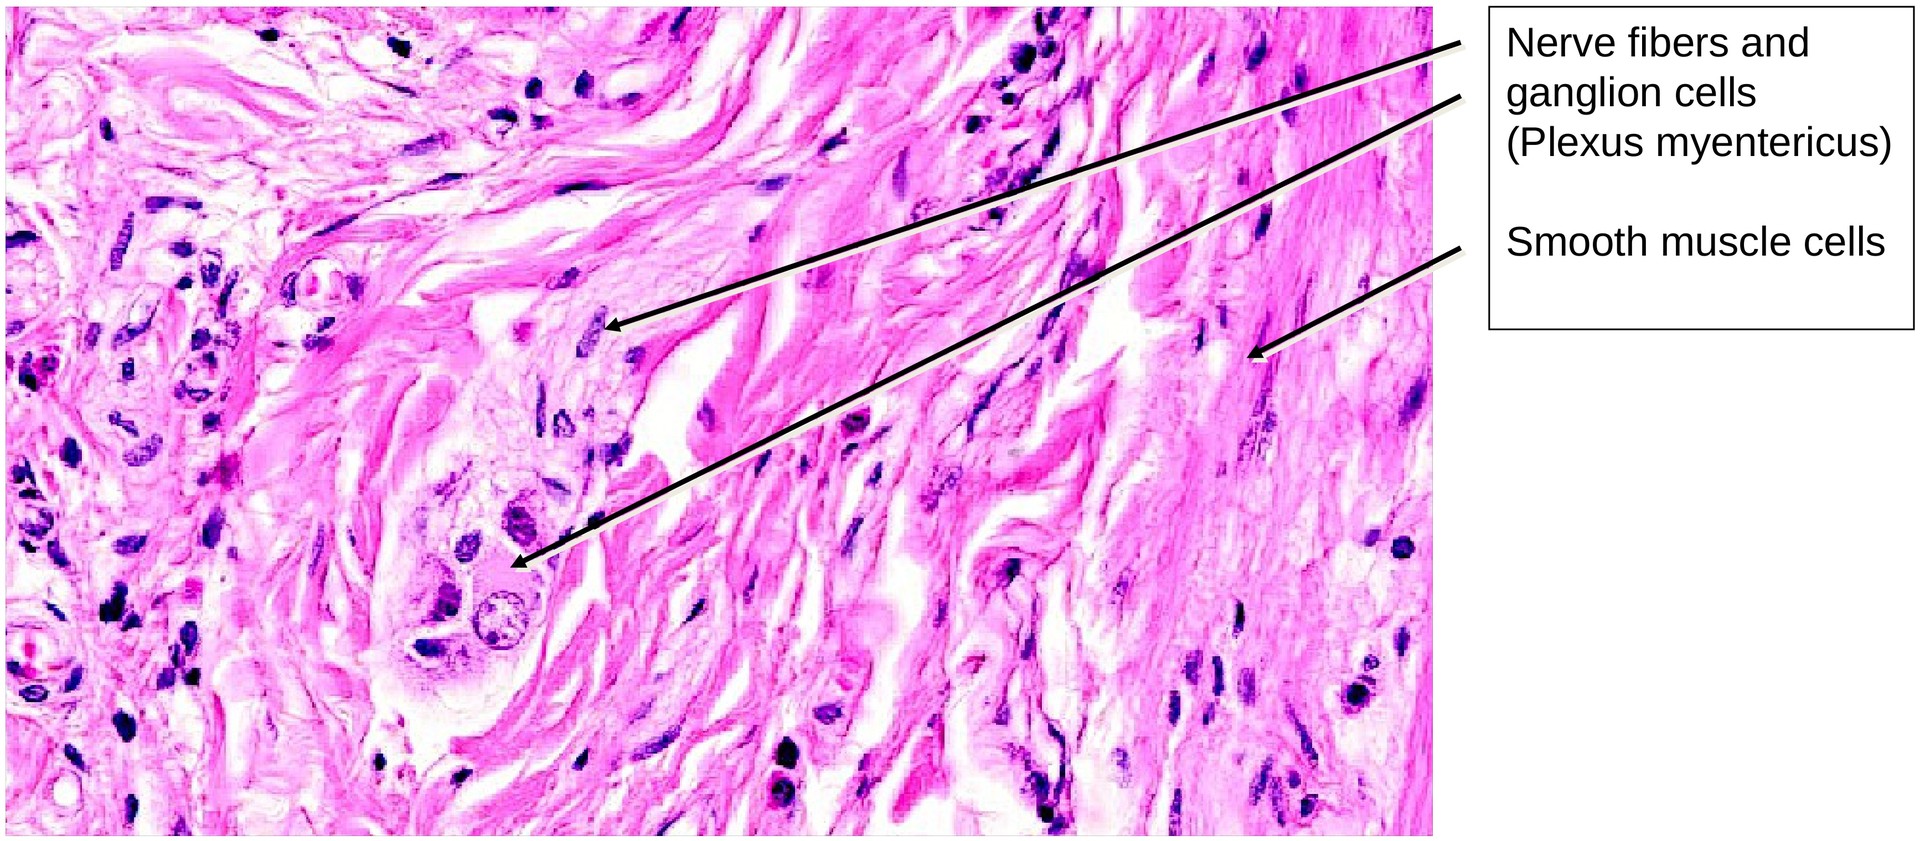

The submucosal plexus (Meissner’s plexus) in the tela submucosa is not as distinct as the myenteric plexus (Auerbach’s plexus), which lies between the circular and longitudinal muscle layers and contains ganglion cells at various points.